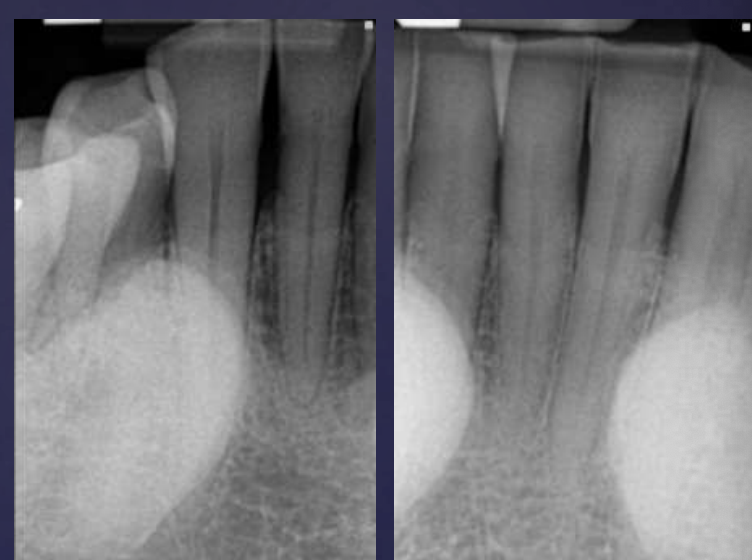

how do ameloblastomas radiographically present?

well circumscribed, corticated

radiolucent

unilocular/multilocular (coarse/curved septae)

expansile

Tooth displacement/root resorption

Pericoronal/mural; impacted tooth

Displacement of #32

Osseous expansion

Thinning of cortices

Displacement of inferior alveolar nerve canal

Multilocular

Root resorption

Thinning of inferior mandibular border

Septae appear coarse

Displacement of teeth